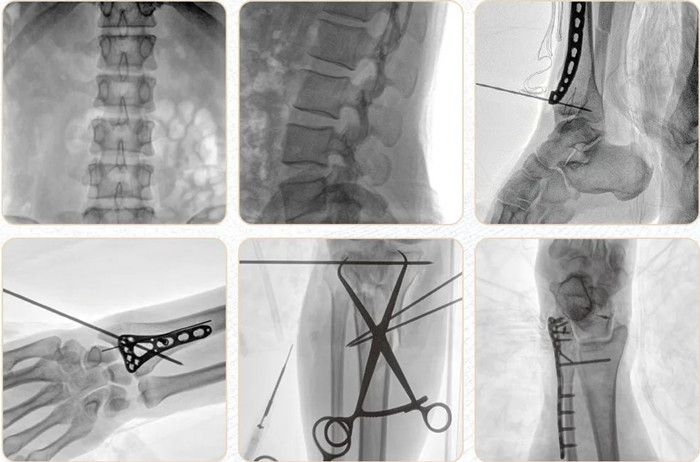

移動式平板C形臂PLX118F-Plus臨床應用范圍:可應用在骨科、普通外科、矯形外科、創傷外科、泌尿外科、脊柱外科、疼痛外科、消化科、腫瘤科、婦產科等科室。

普愛醫療移動式平板C形臂Plus系列搭配高端進口平板探測器,更高的空間分辨率讓臨床圖像更加清晰銳利,更高的密度分辨率讓不同組織的圖像層次分明,更強的信號處理能力可以讓設備用更低的劑量即可呈現優質的圖像。

圖像后處理采用多層圖像處理技術,將曝光后的圖像自動進行分層處理,大大降低了噪聲對圖像的影響,確保了每張圖像的呈現效果。